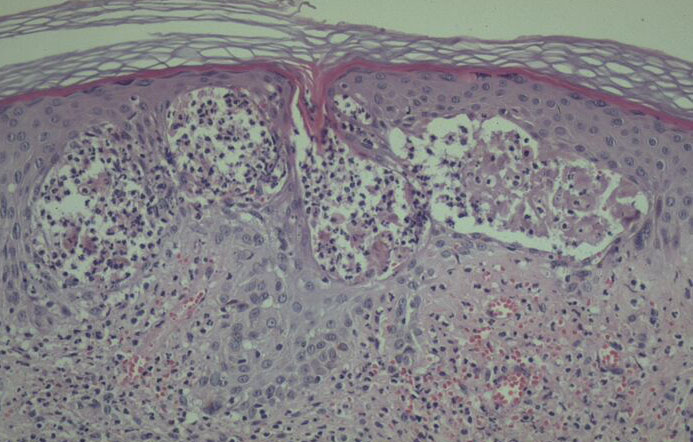

Histology. The main, very characteristic, histologic abnormality is that of progressive intra- and intercellular epidermal edema leading to prominent reticular degeneration, vesiculation, and finally confluent epidermal necrosis . The vesicles contain fibrin and acute inflammatory cells and overlie a dermal cellular infiltrate of predominantly perivascular lymphocytes, histiocytes, and neutrophils . A vasculitis is not seen. In some cases, there is focal necrosis of the superficial dermis. Prominent secondary changes in late lesions may obscure the characteristic findings. |

photodermatoses by its clinical features and largely diagnostic histopathology, provided that appropriate viral studies, blood, urine, and stool porphyrin concentrations as well as circulating antinuclear factor and extractable nuclear antibody titers are also normal. The pattern of necrosis is remarkably similar to that seen in viral (including herpetic) infections and hand, foot, and mouth disease. Nevertheless, distinction from herpetic infection is easy, as HV lesional biopsies lack viral inclusions, multinucleated keratinocytes, and nuclei with ground glass appearance; also, hair follicle necrosis is lacking. However, distinction from hand, foot, and mouth disease is more difficult, but the clinical settings of the two diseases are totally different. Finally, a T-cell lymphoma variant with facial necrotic lesions simulating HV has been described in Asian and native Central American Indian children and rarely in adults , but histologic distinction is not difficult, as atypical lymphoid cells are readily apparent in the lymphomatous infiltrate. |